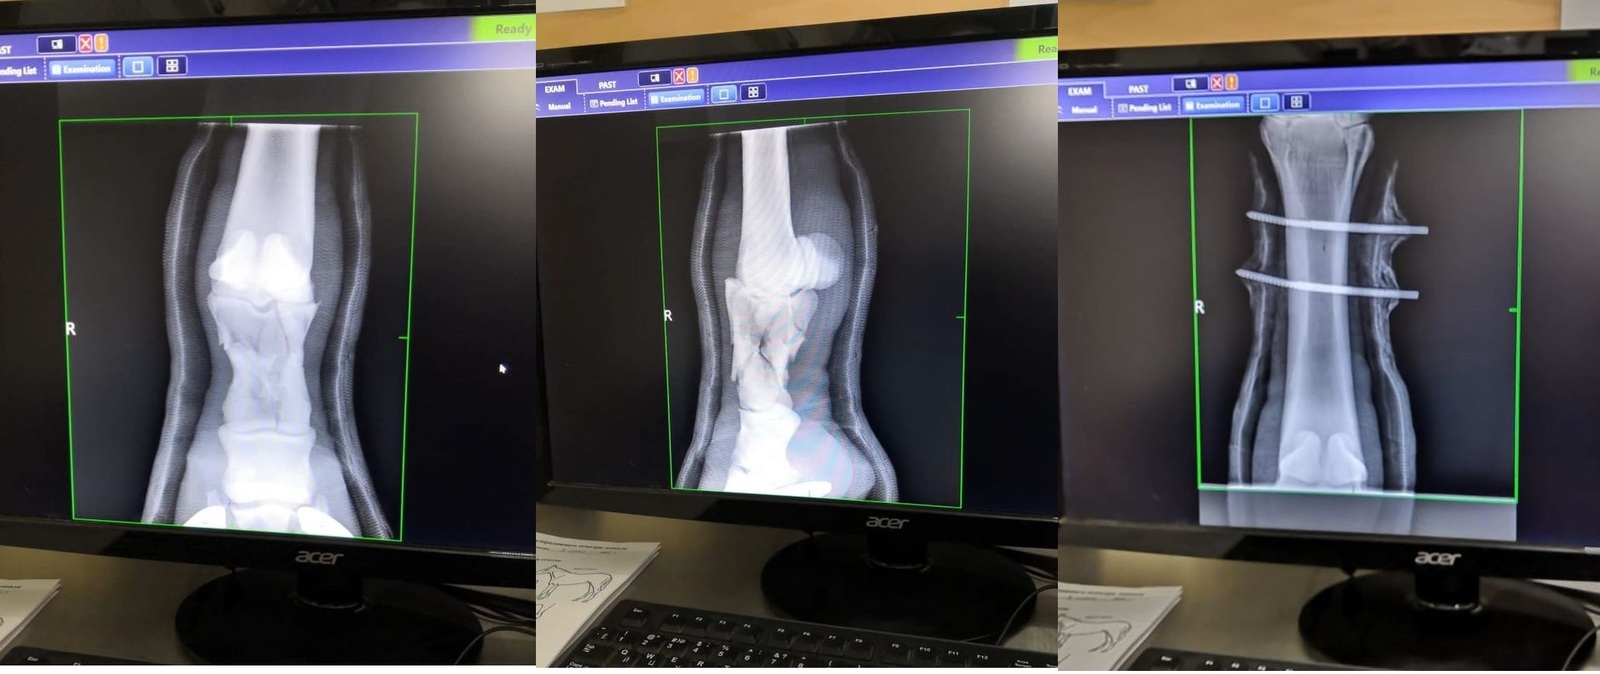

Снимки

Ногу собрали

Одним из последних ветеринарных достижений при лечении переломов у лошадей, является метод транскортикальной (чрезкостной) фиксации. Смысл такой фиксации заключается в том, что выше места перелома внутри кости временно ставят специальные металлические стержни, а потом всю конечность одевают в легкий и вместе с тем очень прочный полимерный гипс, в котором и закрепляют эти стержни. Таким образом, получается, что конечность лошади выше места перелома как бы подвешивается внутри гипсовой повязки. В результате этого лошадь получает возможность полностью опираться на сломанную конечность, так как весь ее вес при этом ложится только на здоровую кость и гипс, а поврежденный участок остается без нагрузки. Устанавливаются такие стержни под общим наркозом, как правило, одновременно с наложением гипса или при проведении операции по остеосинтезу. В настоящее время метод уже достаточно широко апробирован как за рубежом, так и у нас и помог спасти не одну лошадиную жизнь. Во многом, только благодаря транскортикальной фиксации у врачей появился шанс бороться за жизни лошадей даже при таких серьезных травмах, как полный перелом пястной или плюсневой костей. Источник 2009 год